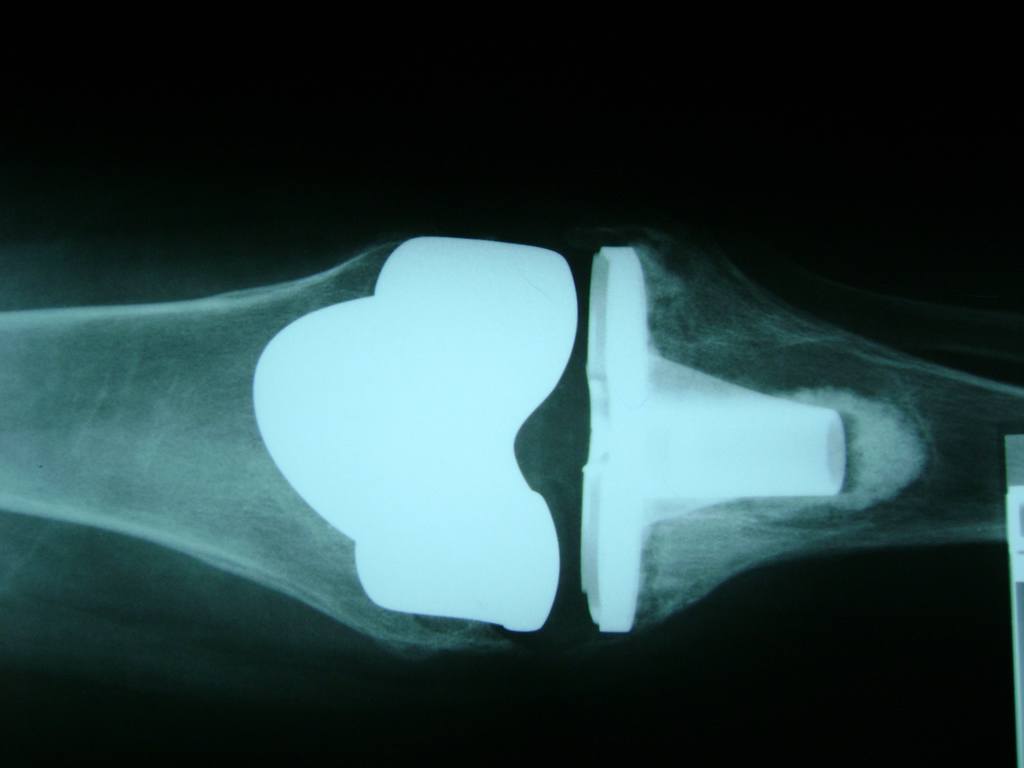

Cirugía de Fémur - Rodilla

La artroscopia de rodilla es un cirugía en el cual la estructura interna de la articulación es examinada ya sea para realizar un diagnostico o para realizar un tratamiento, este procedimiento se realiza utilizando un instrumento parecido a un pequeño tubo llamado artroscopio.